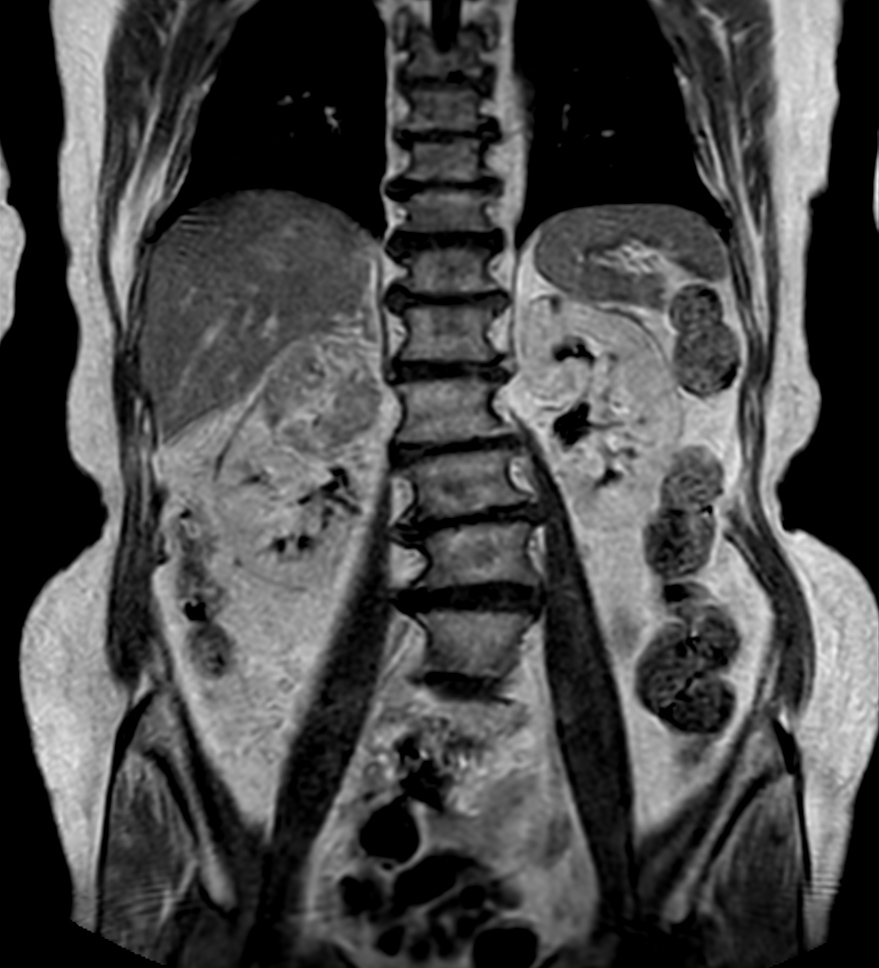

Patient with a kidney lesion. The ExamCard includes techniques for 3D imaging (PelvisVIEW, eTHRIVE) allowing for multiple image directions in one single scan, efficient fat-free imaging over large field-of-views (mDIXON XD), a multi-phase contrast-enhanced sequence (4D FreeBreathing) to improve imaging confidence and Compressed SENSE to accelerate the entire exam.

T2w TSE